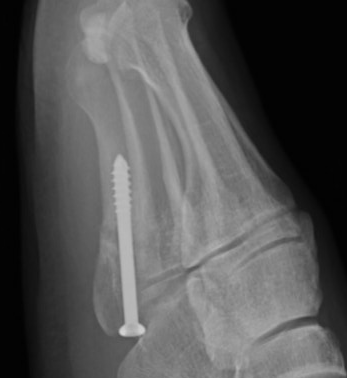

Intramedullary Screw

Screw fixation Zone 2 nonunion

Screw fixation Zone 3 nonunion